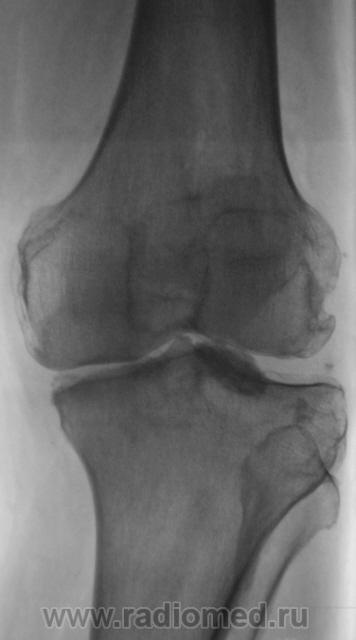

Пациент направлен в рентгеновский кабинет врачом хирургом для рентгенографии коленного сустава. Пациента в течение 2-х лет беспокоят боли в коленном суставе "Тупого характера". Хирургом выставлен диагноз - "Деформирующий артроз". Произведены рентгенограммы.

Свободное внутрисуставное тело.

Вы сами сказали - "хондроматоз", что по всей видимости, не подразумевает "узкую локальность", а сдесь только в одном месте. А может это, что-то типа оторвавшегося куска "мениска", и в результате травмы "пропитавшееся"солями извести?

Вполне возможно. Но и при хондроматозе не все внутрисуставные тела выявляются рентгенологически, часть их не видна. Хотя, хондроматоз маловероятен.

А термин "суставная мышь" не подойдет? Или он уже не используется?

Да нет, используется и весьма часто, особенно тогда, когда затруднительно конретизировать. Но "мышь" какая-то уж сильно плотная, прямо - пропитанная "мумия" мыши.

Согласен по поводу мениска -- вероятно, фрагмент медиального. И обратите внимание на мелкую тень с латеральной стороны -- то ли ещё одно свободное тело, то ли обызвествление в толще латерального мениска.

upd: перечитал пост -- засомневался: неужели свободное тело за два года дало только "тупые боли"?